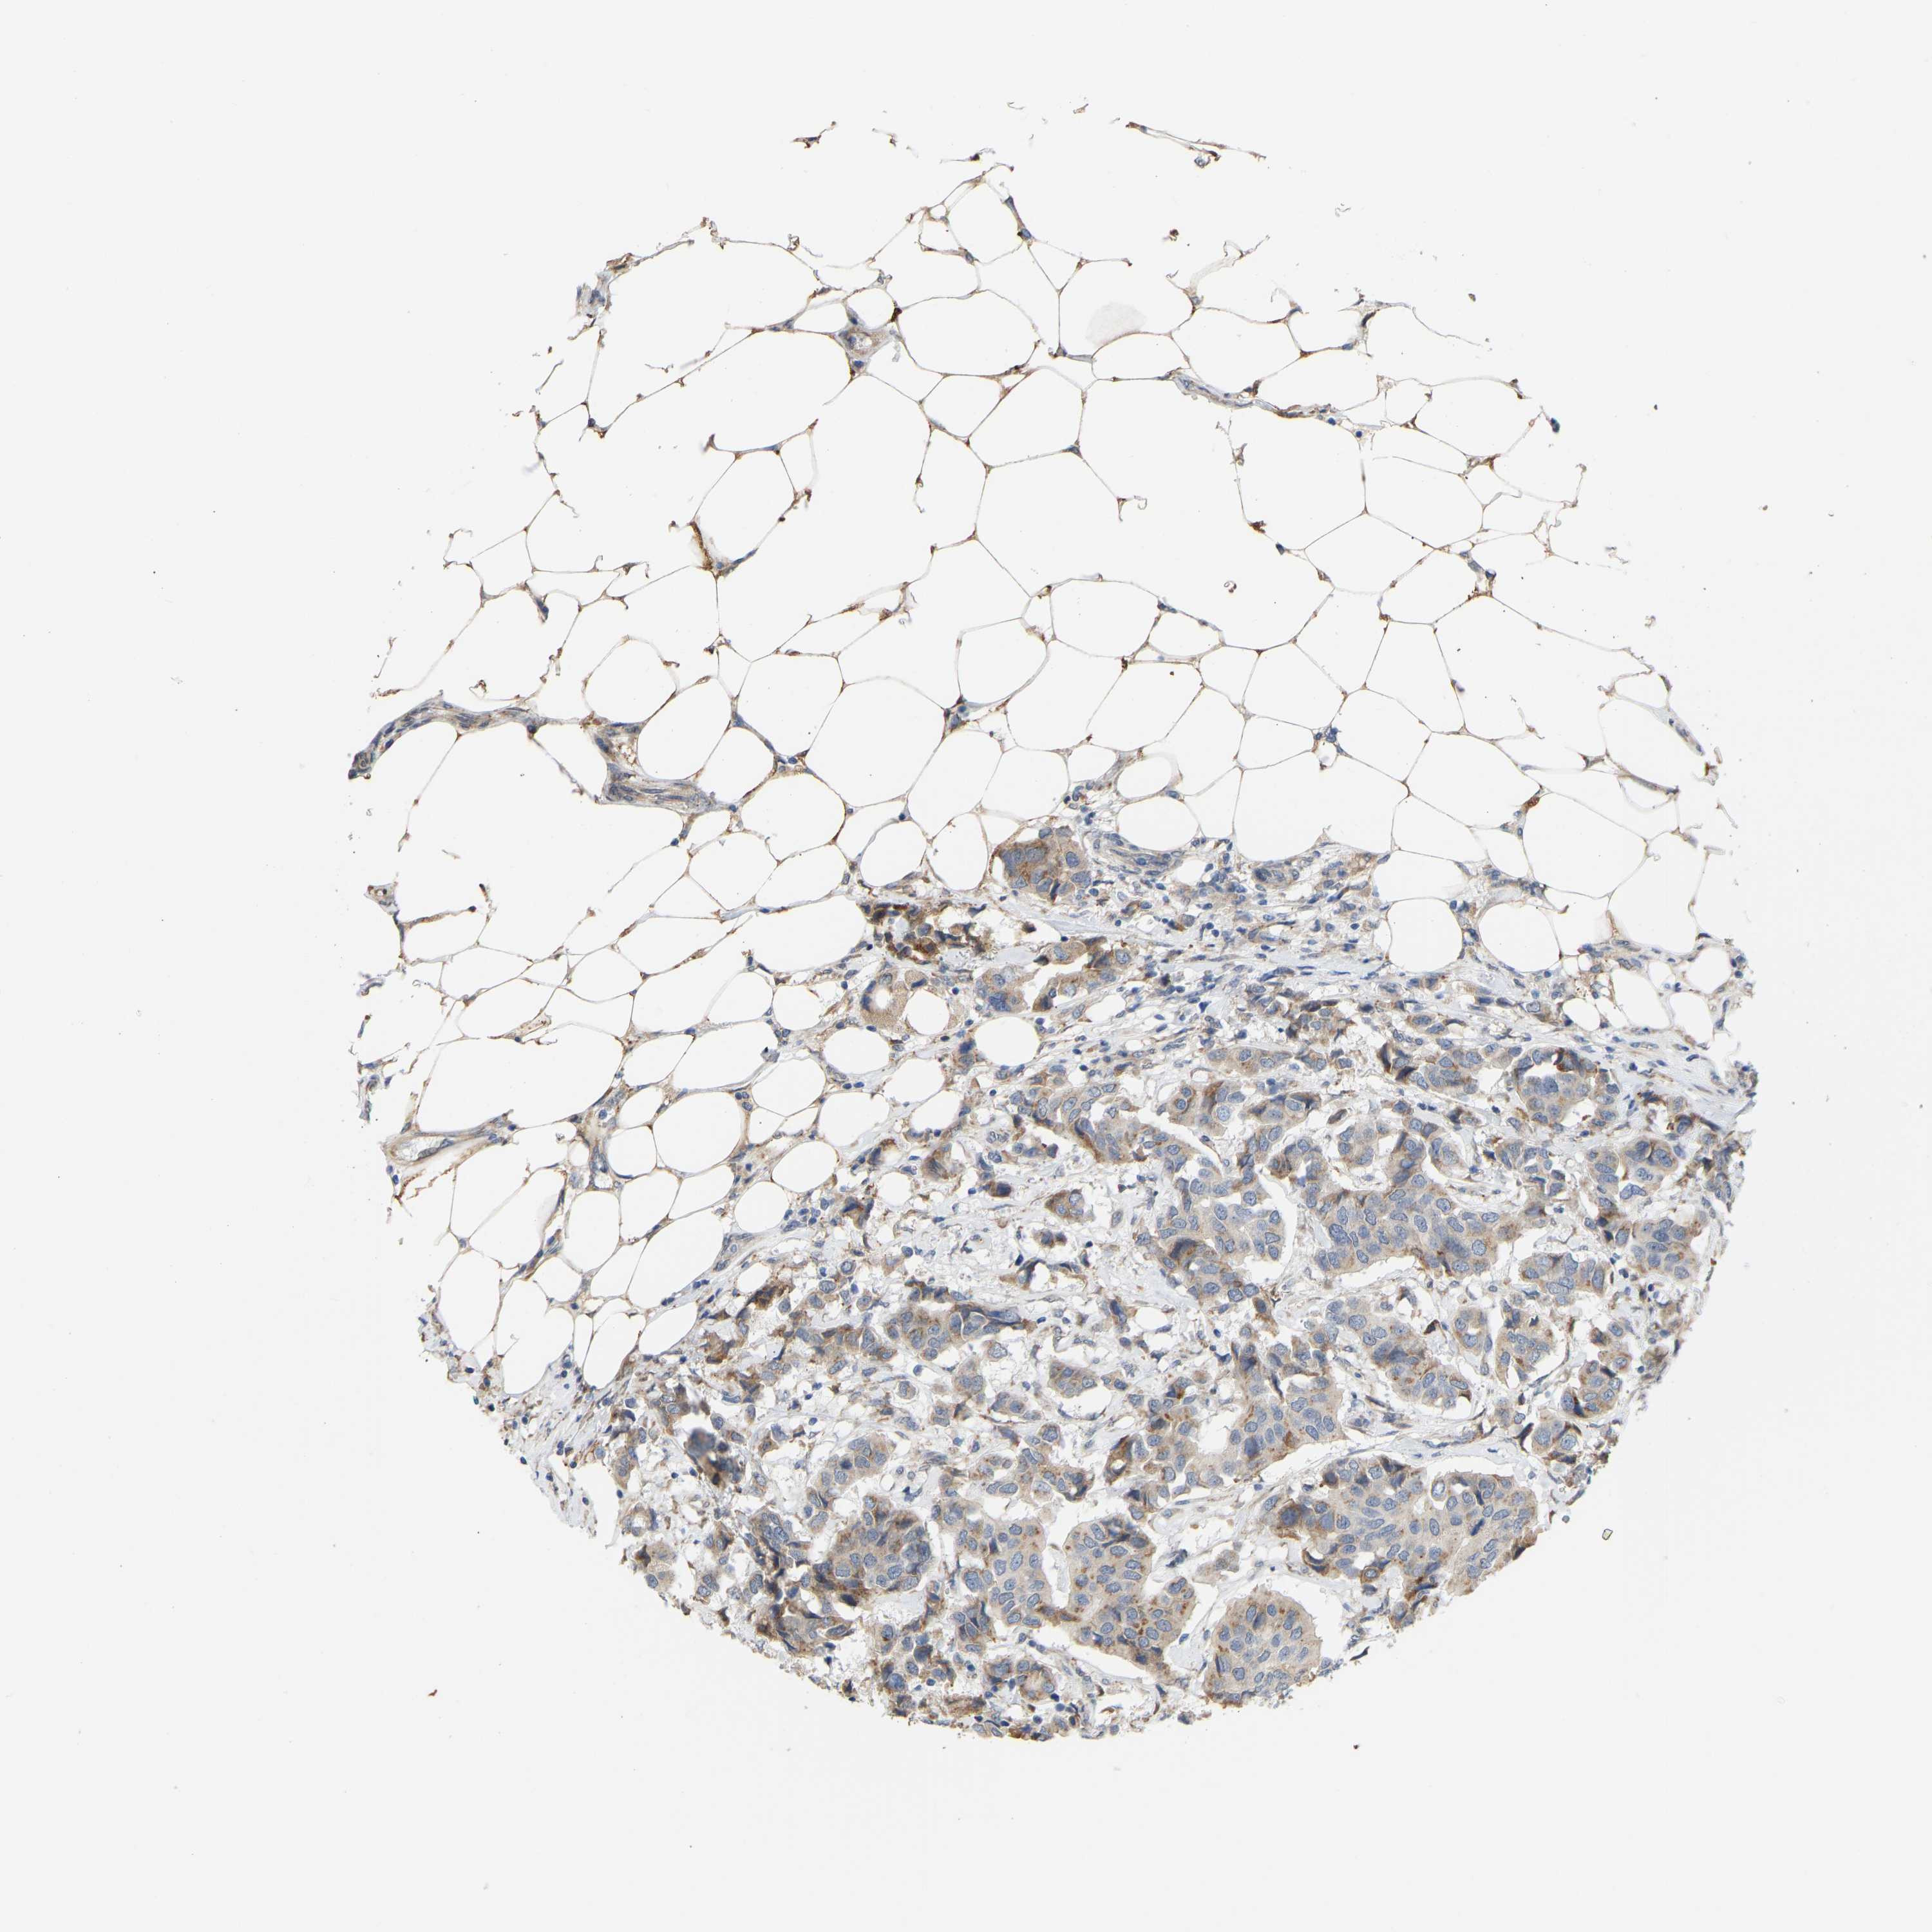

CANCER BREAST CANCER Show tissue menu

BRCA TCGA BRCA VALIDATION PROTEIN EXPRESSION